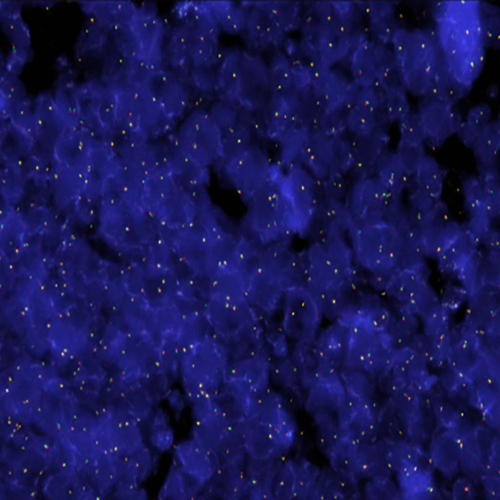

Hybridization of RET break probe to a tissue section showing abarrant pattern (1RG1R1G).

Pericentric inversion of chromosome 10 involving the RET (ret proto-oncogene) gene at chromosome 10q11 is known to increase expression of the RET gene by fusion with KIF5B (10p11). Translocations with other fusion partners have also been described. Elevated expression of RET is observed in non-small cell lung cancer (NSCLC). Translocations involving RET have also been described in thyroid carcinomas. The RET (10q11) Break probe is optimized to detect translocations involving the RET gene region at 10q11.